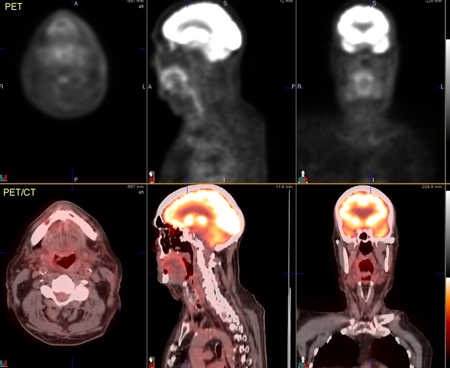

[Figure caption and citation for the preceding image starts]: 74-year-old man with squamous cell carcinoma of the left tongue base extending into the hypopharynx. Images after chemoradiotherapy, showing complete resolution of metabolic foci. Mild diffuse increased metabolism in the oropharyngeal region consistent with mild post-therapy inflammationFrom the collection of Dr Fabio Almeida; used with permission [Citation ends].